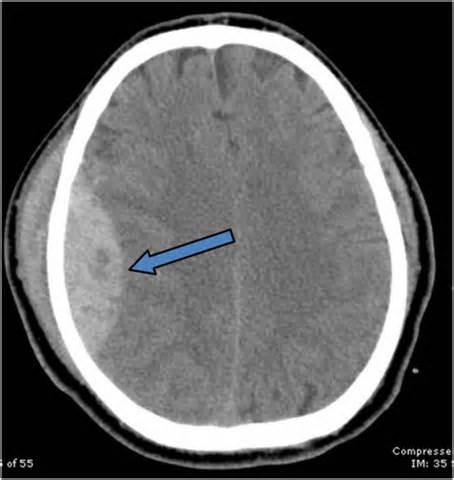

Чтобы диагностировать наличие эпидуральной гематомы, специалисту необходимо провести осмотр пациента. Для детального изучения гематомы, ее места локации и размера необходимо провести МРТ или КТ.

Эпидуральная гематома на КТ.